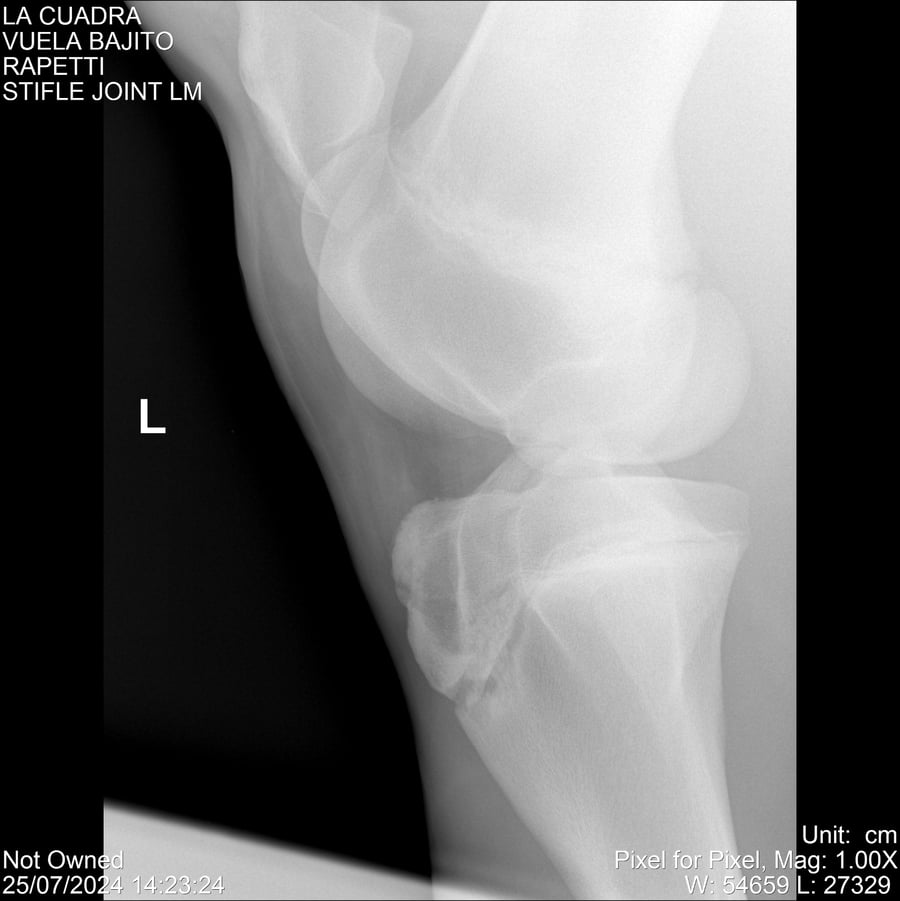

LOTE 16, VUELA BAJITO Lote Anterior Volver al remate Lote Siguiente Ficha Contacto Montevideo - Ficha del Lote Identificador: #284451 Categoría: Yeguarizos Montevideo - 77 Visualizaciones ClicData Contacto Empresa: Abelenda N. R., Walter Hugo Nombre*: Teléfono* : E-mail* : Mensaje Enviar Registrese gratis Este contenido Exclusivo está disponible sólo para usuarios registrados Ingresar